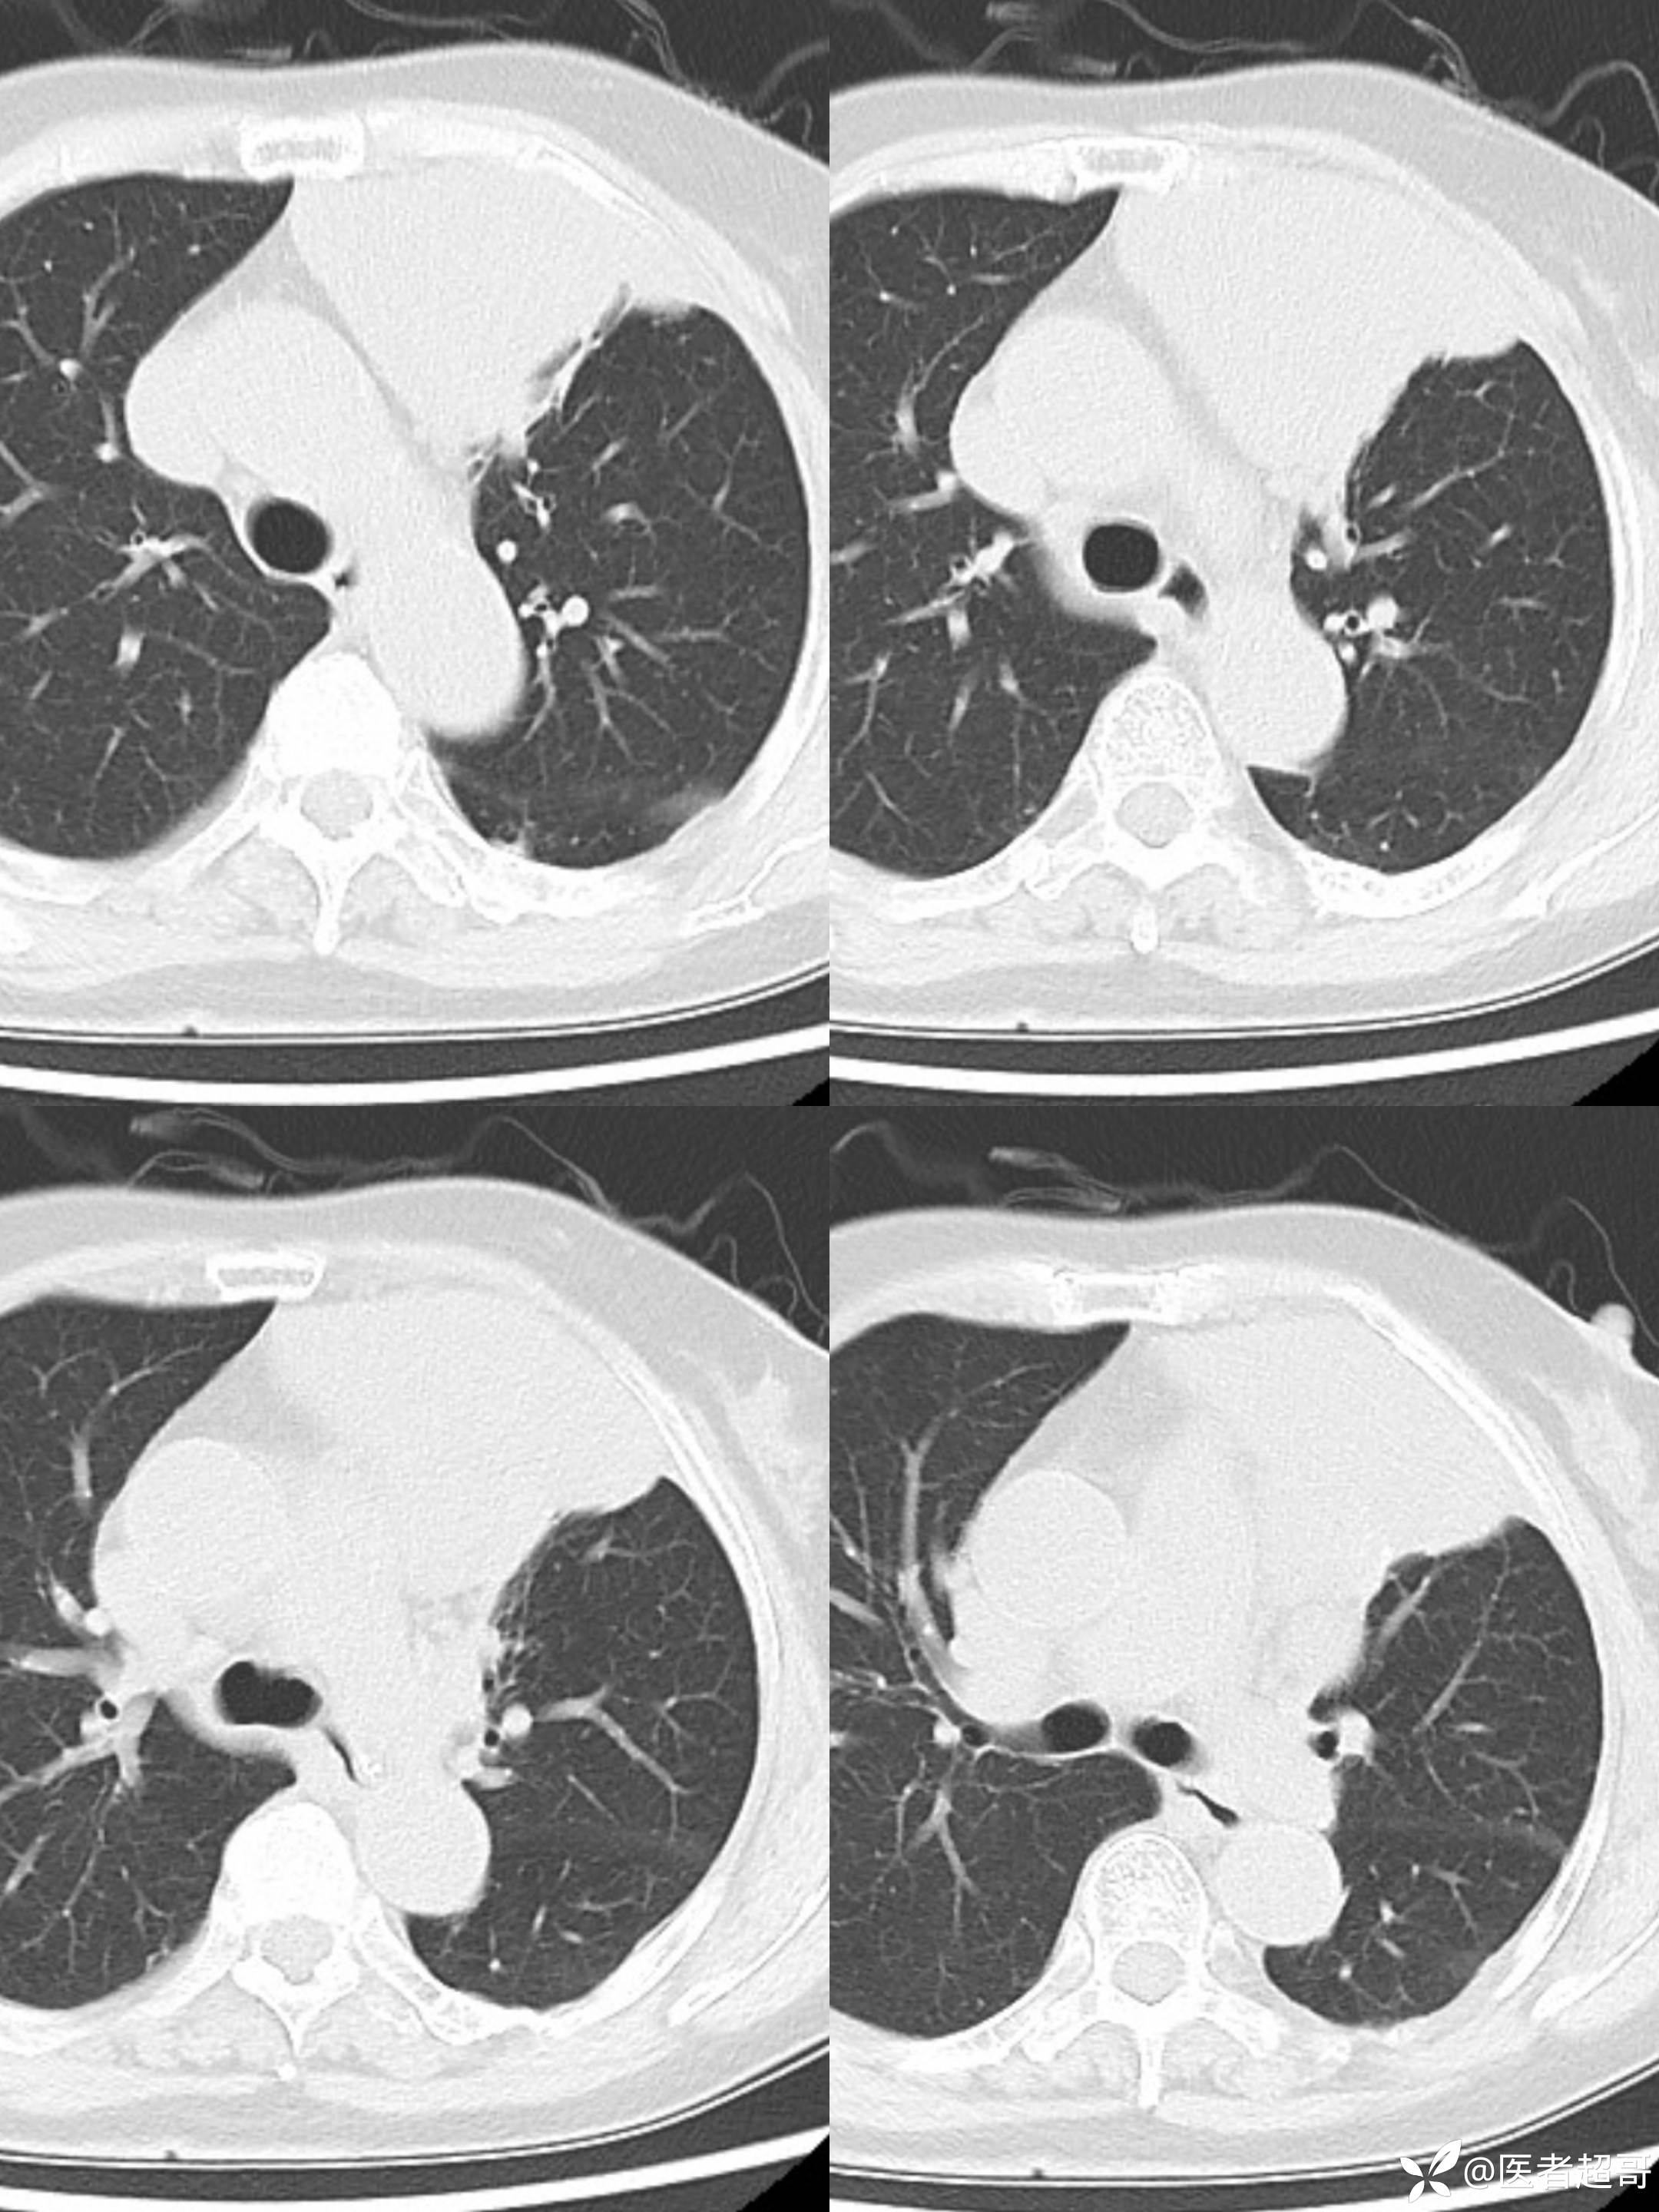

女73岁,体检发现左上纵隔占位1周

患者于1周前体检行CT检查提示:“左上纵隔见不规则团块状软组织密度影,大小约90*63mm”,患者平素偶有头晕,无明显胸闷气急,今为进一步治疗来我院就诊, 门诊以"左上纵隔肿物"收入院。